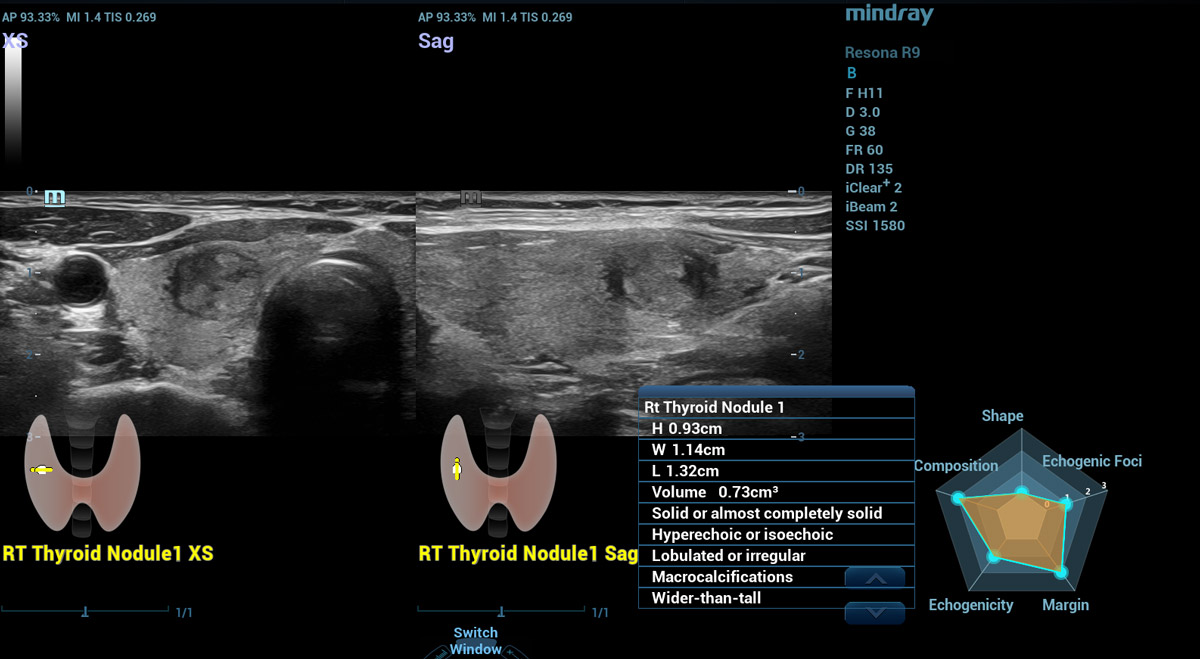

Smart Thyroid

Thyroid is een analyse- en rapportagetool voor de schildklier om de klinische routine van schildklieronderzoeken nauwkeuriger en productiever te maken.

Smart Thyroid-nodule